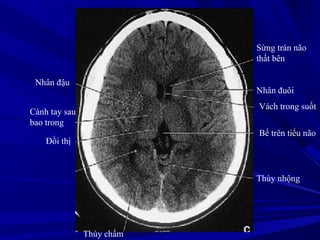

Nhân đậu

Cánh tay sau

bao trong

Đồi thị

Sừng trán não

thất bên

Nhân đuôi

Vách trong suốt

Bể trên tiểu não

Thùy nhộng

Thùy chẩm